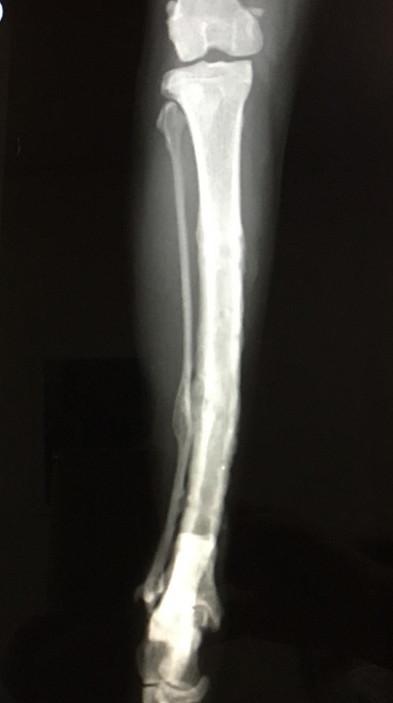

8月21日 手術から 13ヶ月 後

札幌の病院で経過観察、骨形成OKで問題なし。

本当はこの4ヶ月後に再度経過観察って言われたけどとりま完治ってことにするw。